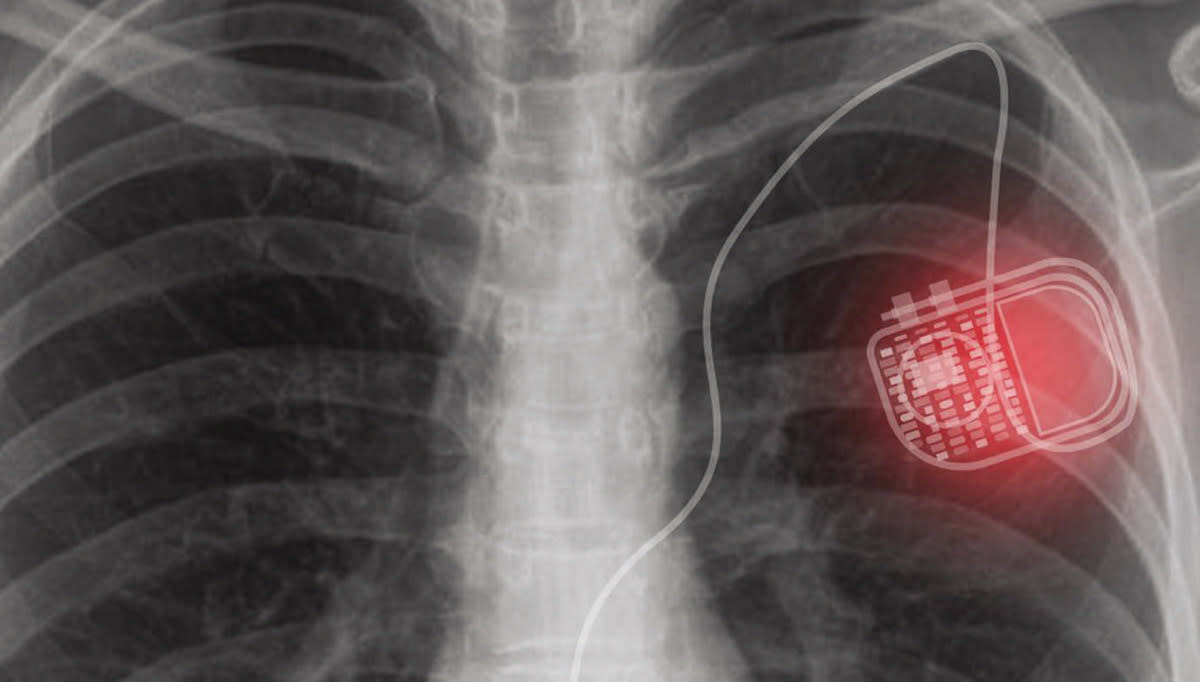

Medical implants such as pacemakers serve various functions in patients and help to improve their quality of life. But to power these devices, re-implants and invasive surgery are often required, which may lead to a risk of surgical complications. In search of a more permanent solution, researchers developed a photonic device that reduces the need for re-implants.

This novel system consists of two parts: a skin-attachable micro-LED source patch, which can generate photons that would penetrate through the tissues, and a photovoltaic device integrated into a medical implant, which can capture the photons and generate electrical energy. This system provides a sustainable way of supplying the medical implant device with enough power to avoid any high-risk replacement methods.